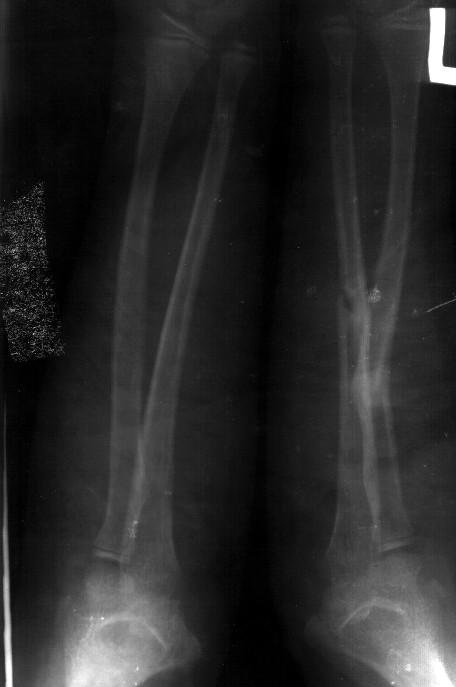

Сделал симметричные снимки с максимальной супинацией и пронацией при согнутом предплечье в 90 град. Объем ротационных движений 90-100 град.

С ув. Сергей Мелашенко

Приморск, Запорожская обл.

Ukraine